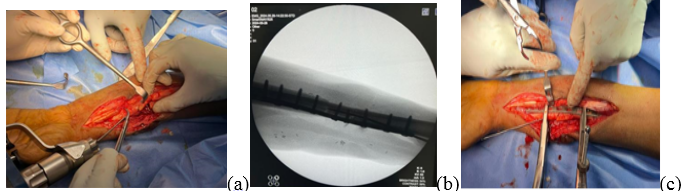

A 52-year-old man was referred to our tertiary care center for a chronic draining wound at the site of a prior open radial shaft fracture. He is a known case of Type 2 diabetes mellitus and is on treatment for the same. The patient initially had a crush injury to the left forearm, which resulted in an absent distal pulse. He was planned for a staged procedure given the Gustilo Type 3C open fracture to achieve an optimal clinical outcome. An external fixator responded by performing a thorough wound debridement, exploration, and bone stabilization. A revascularization procedure was performed by a plastic surgeon on the left forearm, involving primary reconstruction of the left radial and ulnar arteries along with the cephalic vein using a massive saphenous vein graft. Subsequently, a repair of the left median nerve using a cable graft was performed in the initial stage as per damage control orthopedic protocols. Stay sutures were put in, but the defect was not covered. A week later, a groin flap was utilized for coverage of the left forearm. One month after the flap procedure, there was satisfactory flap take-up and no clinical signs of infection; hence, the left groin flap was divided, and the left forearm wound was further debrided and sutured. During this stage, he was planned for definitive fixation of bone; hence, the external fixator was removed. His distal 1/3rd radius fracture with 3 cm bone loss (Fig. 1a and b) was addressed with the volar Henry approach without disturbing the flap extending from the lateral aspect of the radial side to dorsally. He underwent an open reduction internal fixation using a titanium dynamic compression plate, where the 3 cm bone loss was addressed using a fibula strut graft taken from the ipsilateral side (Fig. 2a, b, c).

Figure 2: (a, b, c) Intraoperative images of open reduction internal fixation using fibula strut and primary wound closure.